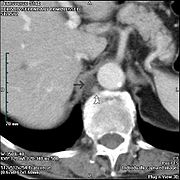

Cisterna chyli is the white bulb in the center near the bottom.

Modes of origin of thoracic duct. a. Thoracic duct. a’. Cisterna chyli. b, c’ Efferent trunks from lateral aortic glands. d. An efferent vessel which pierces the left crus of the diaphragm. e. f. Lateral aortic glands. h. Retroaortic glands. i. Intestinal trunk. j. Descending branch from intercostal lymphatics.

In humans, the cisterna chyli is located posterior to the abdominal aorta on the anterior aspect of the bodies of the first and second lumbar vertebrae (L1 and L2). There it forms the beginning of the primary lymph vessel, the thoracic duct, which transports lymph and chyle from the abdomen via the aortic opening of the diaphragm up to the junction of left subclavian vein and internal jugular veins.[1]